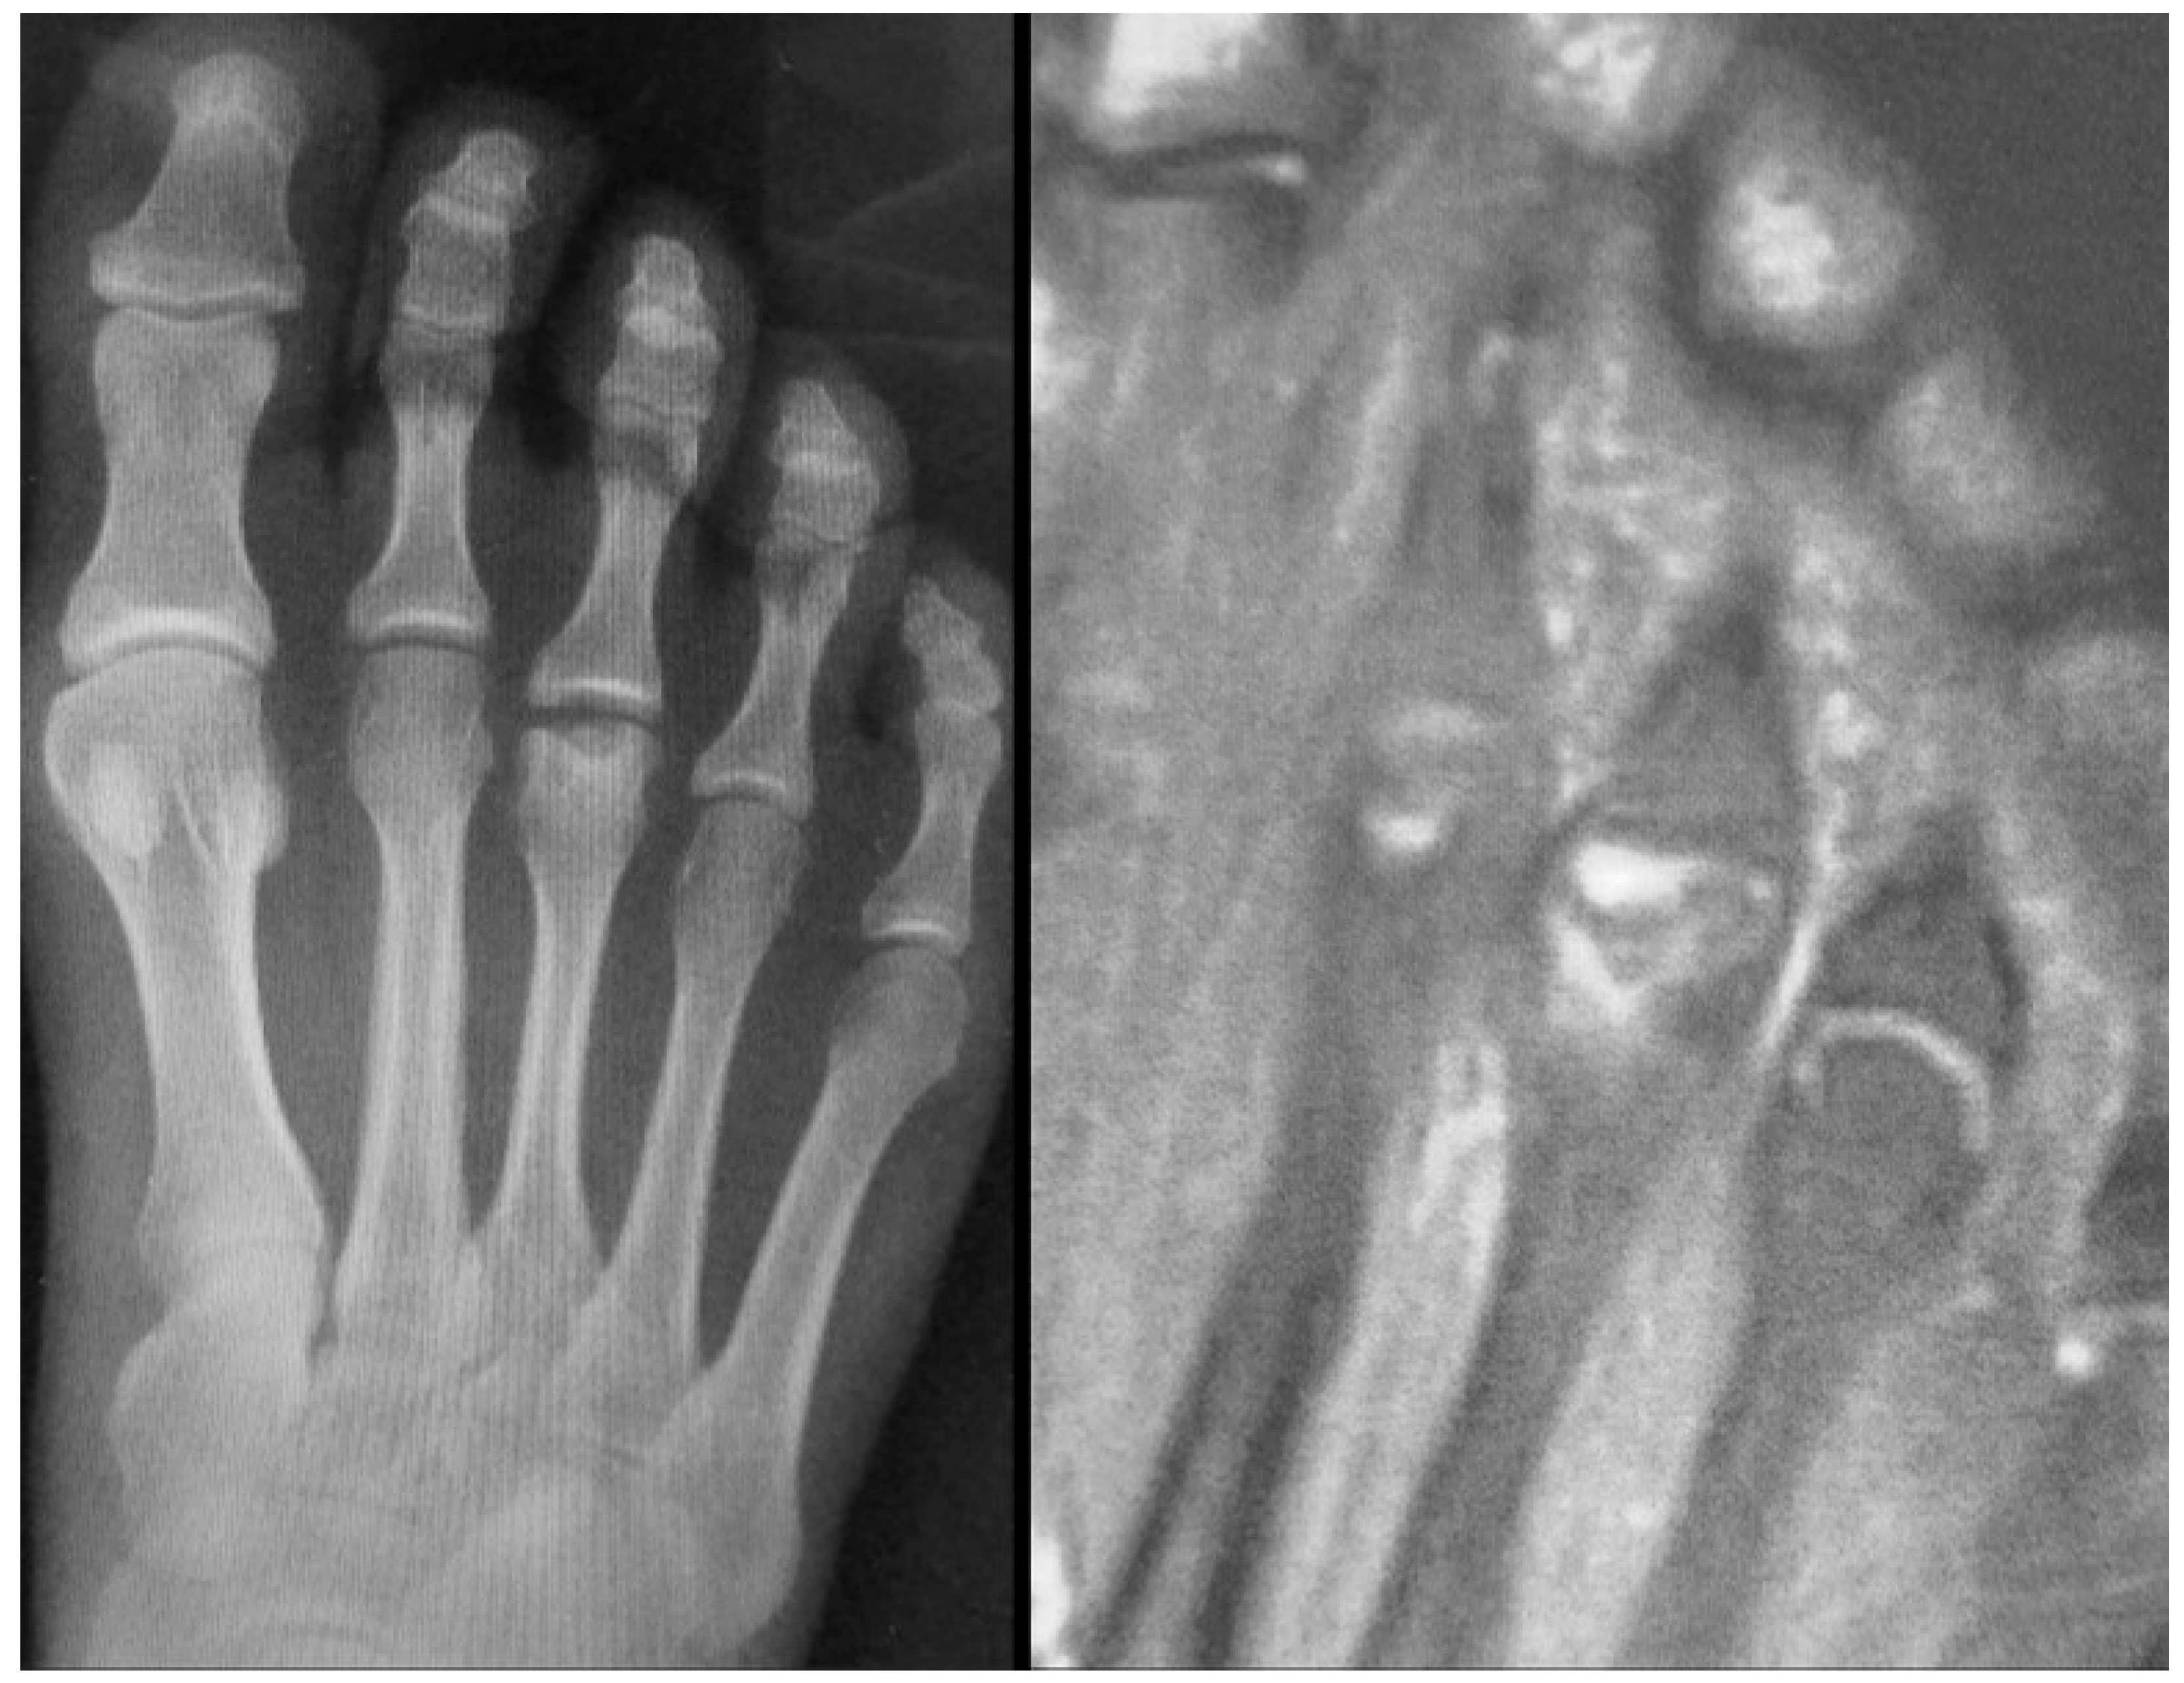

Figure 12.

MRI of a 12-year-old female patient showing extensive bone marrow edema of the third metatarsal head, consistent with active inflammation and necrosis.

If not promptly identified and adequately treated, the condition may progress to severe deformities in adulthood (Figure 13).

Figure 13.

The radiographic progression of the second metatarsal head osteochondrosis in a 22-year-old female patient who had not received any treatment.

In the later stages, radiographs may reveal characteristic changes including subchondral sclerosis, fragmentation, and flattening of the affected metatarsal head (Figure 10 and Figure 11). In some cases, the presence of joint space narrowing or bony irregularities may also be observed. However, early changes, such as bone marrow edema or subtle cartilage damage, may not be visible on standard radiographs. MRI is particularly useful in the early stages of the disease, as it can detect bone marrow edema, which is a sign of active bone inflammation and necrosis, even before structural changes become apparent on radiographs (Figure 10, Figure 11 and Figure 12).